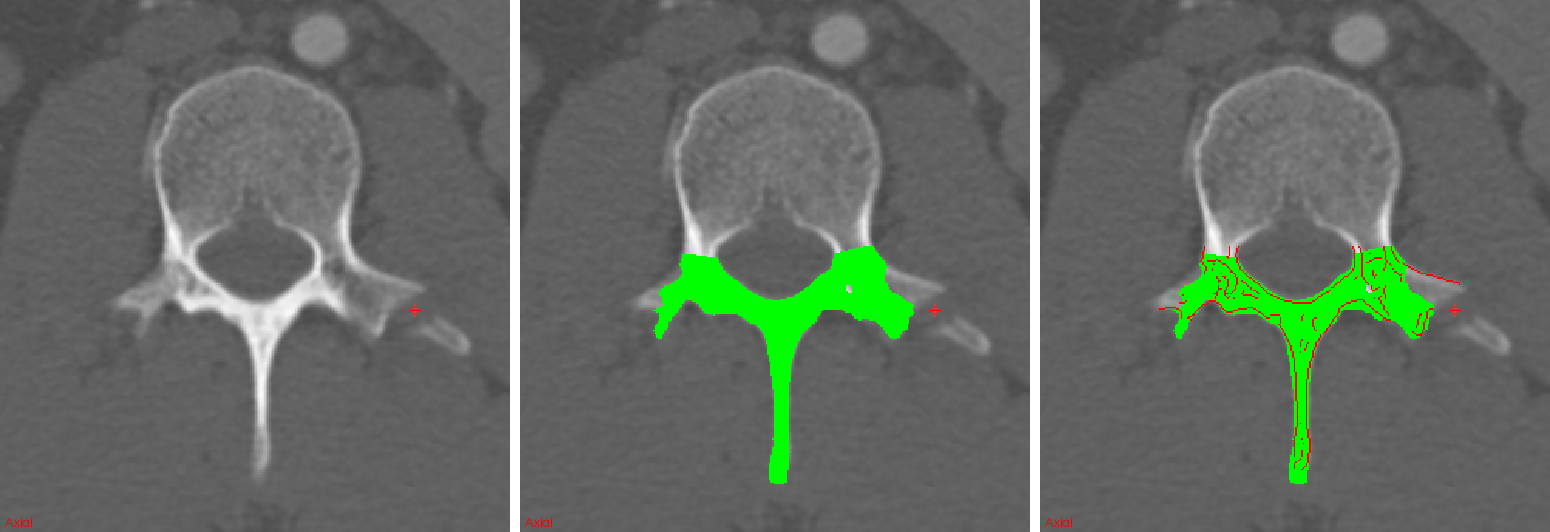

in order to find the horizontal () and vertical () approximations of the image derivative for each CT slice. Here, denotes a convolutional operation. Edge points are located at the maximum of the absolute gradient . The edge maps serve as candidate regions for predicting a set of probabilities for fractures along an image edge using ConvNets. An example of posterior-element segmentation and edge map estimation is shown in Fig. 3.

An experienced radiologist retrospectively marked the location of 55 displaced posterior-element fractures in 18 trauma patients admitted for traumatic emergencies to the University of California-Irvine Medical Center. Image sizes range within and resolutions range within mm. We use a random subset of 12 of these patients with spine fractures for training ConvNets as described in Section 2; 6 patients are reserved for testing. An additional set of 5 spine CTs of healthy patients were added to the training set in order to increase the number of non-fractured examples. A total of 800,000 2.5D patches are randomly selected from the candidate edge maps of the training set and used for learning the ConvNet parameters. After convergence, the ConvNet is applied to a testing case edge map E in order to produce a probability map for fractures. Figure 5 shows examples of probability maps for posterior-element fracture detection along candidate edges. The radiologist’s markings are indicated by crosshairs.